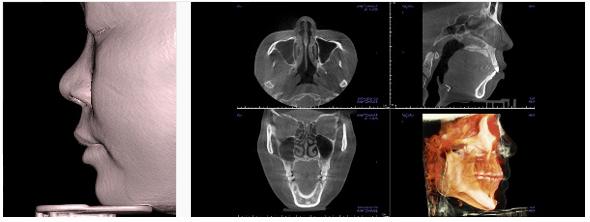

隆鼻手术,采用的3DCT,满足顾客的手术***无误、***可靠。博朗整形外科,在国内***引进隆鼻整形专门3DCT扫描系统,使手术达到正确、***的水准。

1、利用的隆鼻整形专门3DCT扫描,精密分析鼻结构。

在国内的整形外科业界,***实行隆鼻手术患者的立体扫描,不仅了解患者的外鼻,还可以具体分析鼻骨、鼻中隔软骨、下鼻甲介等的状态。

2、***正确的手术计划

利用3D立体映像和鼻内CT映像,分析脸部与外鼻的整体美观,还可以分析鼻骨弯曲、鼻宽、非对称、鹰钩鼻、鼻歪等的程度,并判断是否需要矫正等。还分析鼻中隔软骨的位置、形态、大小、弯曲的程度或损伤的程度等,有助于精密的手术,并达到******的隆鼻手术。